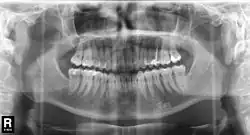

Im November 1895 entdeckte Wilhelm Conrad Röntgen die später nach ihm benannten Röntgenstrahlen, die die Untersuchung des Kiefers vereinfachten. Als Mittel zur örtlichen Betäubung von Zahnschmerzen wurde im Jahre 1905 das Lokalanästhetikum Procain von den deutschen Chemikern Alfred Einhorn und Emil Uhlfelder entwickelt, die dem Wirkstoff den Namen Novocain (lateinische Wortschöpfung für „Neues Cocain“) zuordneten. Damit waren die Grundlagen für eine moderne Diagnostik und Therapie gelegt. Die Zahnheilkunde erlebte daraufhin einen rasanten Fortschritt: von der Entwicklung zahlreicher oralchirurgischer Verfahren bis zur Anfertigung von Zahnersatz mittels CAD/CAM-Verfahren. Parallel zum Fortschritt der wissenschaftlichen Zahnheilkunde entwickelte sich das Berufsbild, was in der Geschichte des Zahnarztberufs dargestellt wird. Daneben entwickelte sich die Tierzahnheilkunde, die sich entsprechend modifizierter Verfahren der allgemeinen Zahnheilkunde bedient.